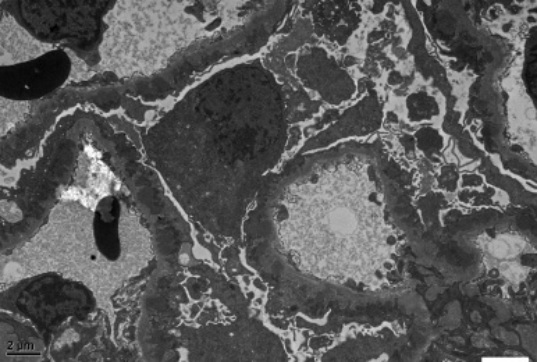

部分超微病理电镜图示例:

图1 肾脏病